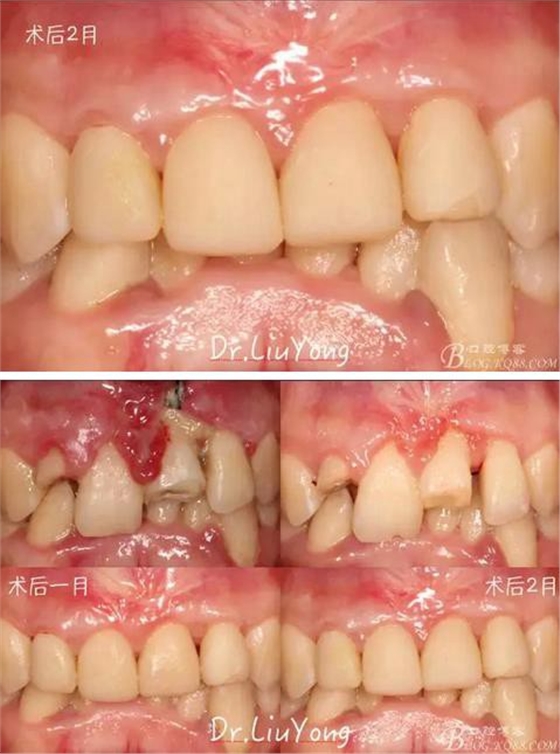

膜齦手術后2月復查,可以明顯觀察到,B12之間的牙齦乳頭明顯高度增加,黑三角得到很大改善,如下圖:

術后兩周,復查,A1達到了完全的根面覆蓋,B1牙齦退縮由原來的3.5mm減少到1mm,B2近中牙齦也得到部分的恢復,同時所有牙齦邊緣都通過手術增厚。如上圖